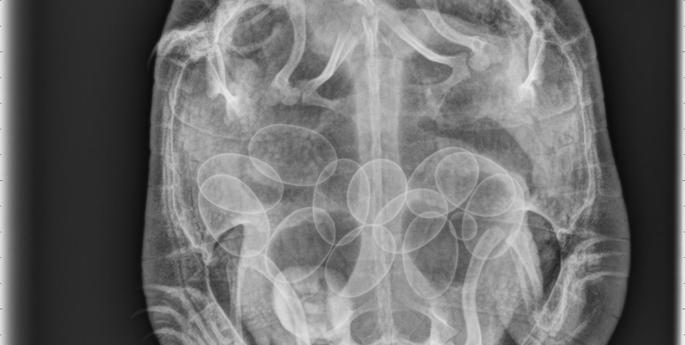

Vet staff got a bit more than expected when this turtle recovered at Taronga Western Plains Zoo Wild Life Hospital.